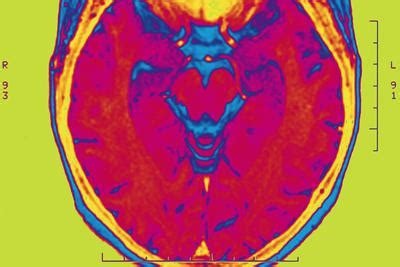

目前,科学家对人脑的研究表明,人脑分为左右脑。左脑主要从事逻辑思维和有序思维;右脑主要从事形象思维、创意源泉、是艺术和经验学习的中枢,右脑的存储量是左脑的100万倍。科学家进一步发现,现实生活中95%的人只使用左脑。科学家们指出,大多数人一生中只使用大脑的3-4%,剩下的97%隐藏在右脑的潜意识中。

一些专家指出,我们的传统教育是通过实践、反复、测试等方法传授知识给学生,这些实践是在左脑的训练和发展;人们右脑的发展和对儿童的训练,由于认识不足、重视度不够、缺乏总结等原因,右脑的潜能还远远没有得到开发和发展利用。日本著名右脑专家七田真教授通过大量的调查发现:人类大脑在3岁之前发育60%,在6岁之前发育90%;右脑在3岁之前发育,而左脑在4岁发育。但是成年后的右脑只有三岁左右的四分之一!实践表明,如果不从小培养和训练右脑潜能,在发育过程中会逐渐丧失。

目前,人们对左脑和右脑的理解是:一,左脑,又称理性脑或语言脑,指挥语言、文字、符号、分析、判断、立体认识的逻辑思维,并直接指导身体右侧的运动功能。第二,右脑,又称感性脑或形象脑,负责音乐、图形、色彩、形象、情感、非言语概念、空间意识、想象等。它直接指导身体左侧的运动功能。它充满了好奇心和创造力。它直观地观察事物,调查整个情况。这些是右脑的功能。

在科学研究和实践中,人们越来越意识到右脑的特点和重要性:第一,在右脑中记忆知识,特别是对逻辑知识含量较低的人来说,更容易、更牢固;第二,右脑是是创造力的源泉,但传统的教育使绝大多数人习惯于用左脑和游走右脑。大脑,所以增加右脑的发育和训练是非常重要的。第三,左脑和右脑是相互协同工作的,一般来说,右脑的形象思维会产生新的想法,而左脑则会以语言的形式表达出来。